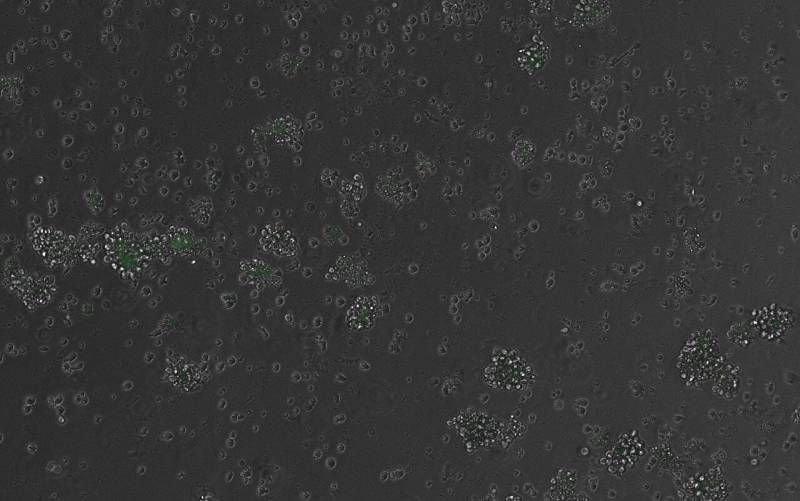

В журнале Cell вышло исследование, описывающее, что генеративный ИИ смог успешно разработать исусственные молекулы, способные контролировать экспрессию генов в здоровых клетках млекопитающих. Ученые из Центра геномного регулирования (Испания) создали ИИ-инструмент, генерирующий ранее невиданные в природе ДНК-регуляторные последовательности. Модель может создавать фрагменты ДНК с заданными критериями. Например, включить в стволовых клетках ген, чтобы те превратились в эритроциты, но не в тромбоциты.Модель предсказывает комбинации «букв» ДНК (нуклеотидных оснований: A, T, C, G), необходимые для требуемых схем экспрессии генов в конкретных типах клеток. Ученые синтезировали примерно 250-буквенные фрагменты ДНК химическим путем и добавлили их в вирус для доставки в клетки.Исследователи попросили ИИ спроектировать синтетические фрагменты, активирующие ген, кодирующий флуоресцентный белок в некоторых клетках, не изменяя экспрессию генов. Фрагменты были созданы с нуля и внедрены в клетки крови мышей, где последовательности слились с геномом в случайных местах. Эксперименты прошли успешно, и дали предсказанный эффект.

На протяжении пяти лет команда синтезировала более 64 тысяч синтетических энхансеров. Это самая большая библиотека синтетических энхансеров в клетках крови на сегодняшний день. После внедрения в клетки ученые отслеживали, как каждый искусственный энхансер работал на протяжении семи стадий развития клеток крови. Они обнаружили, что многие энхансеры, когда активируют гены в одном типе клеток, подавляют их в другом.